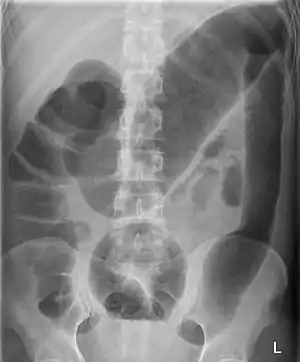

| Toxic megacolon associated with ulcerative colitis. | |

A human colon is considered abnormally enlarged if it has a diameter greater than 12 cm[3] in the cecum (it is usually less than 9 cm[4]), greater than 6.5 cm[3] in the rectosigmoid region and greater than 8 cm[3] for the ascending colon. The transverse colon is usually less than 6 cm in diameter.[4]